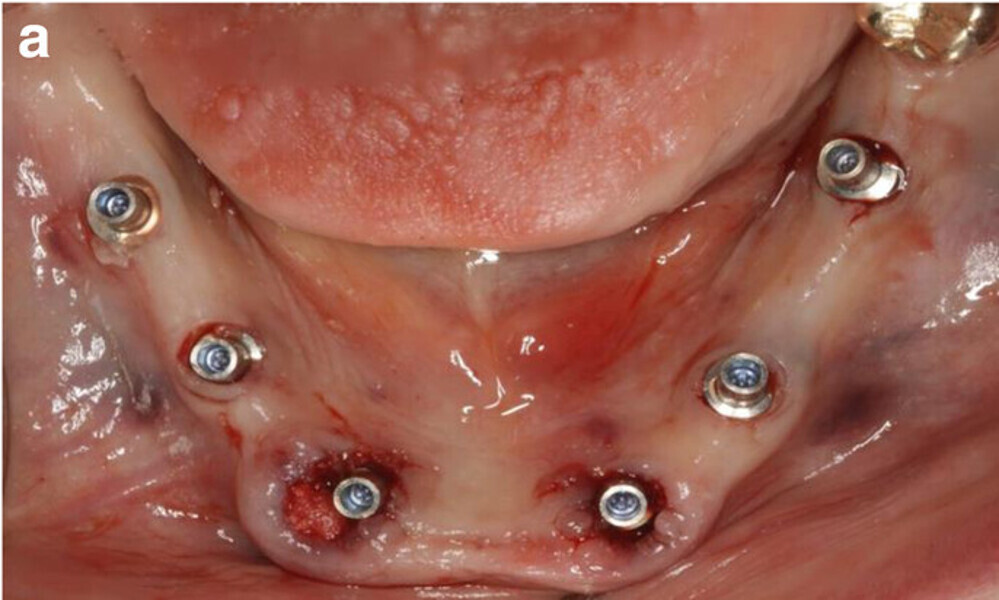

Fig. 9a: Occlusal views of the abutments (a) and of the immediate provisional restoration that were passively bonded in situ (b).

Fig. 9b: Occlusal views of the abutments (a) and of the immediate provisional restoration that were passively bonded in situ (b).